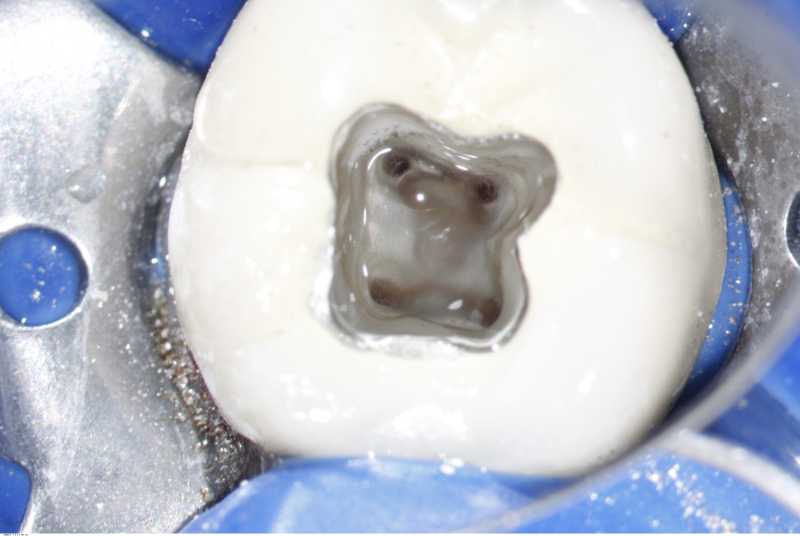

Inicio Especialidades Endodontia